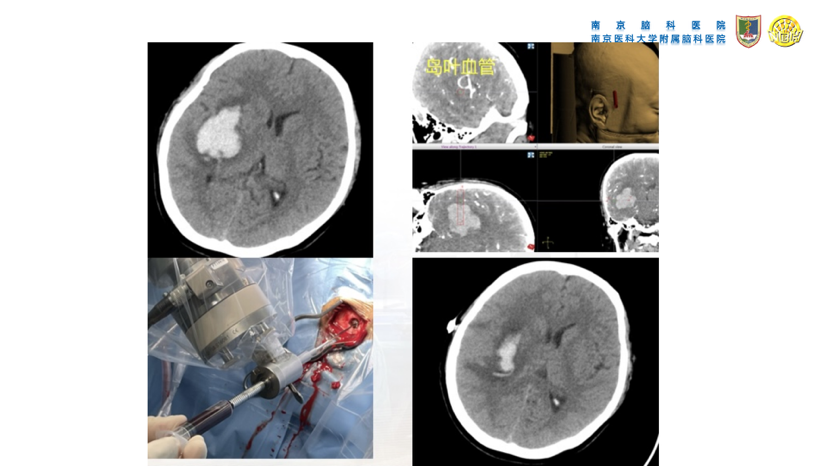

高血压性脑出血的微创手术治疗(高血压性脑出血的血压管理、镇静镇痛处理、手术指征、手术方法等重要问题)